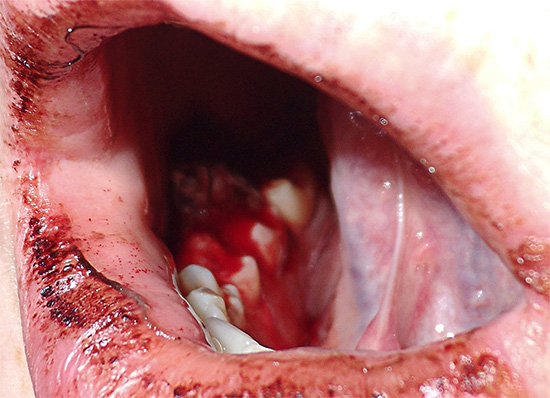

La foto sotto mostra le fasi iniziali della procedura per la rimozione del dente del giudizio retinirovannogo (cioè nascosto sotto la gomma):